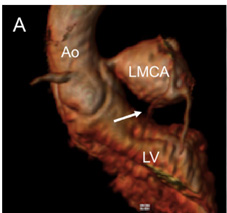

Coronary Problems

Description: The coronary arteries provide blood supply to the heart. Children can have coronary problems that are different from adults. Children can be born with the coronary arteries in the wrong location, called an anomalous coronary. Children can also have Kawasaki Disease which occurs with a prolonged fever and sometimes causes the coronary arteries to become abnormally large or form aneurysms.

Why MRI: Heart MRI is used to see if the coronary arteries are in the correct location and if there may be a risk of blocking flow. Heart MRI can also look for any abnormal enlargement. Sometimes a medication can be given through an IV to perform a stress test to see if there are problems with blood flow in the coronary arteries when the heart is working harder.

Images: Anomalous left or right coronary, Kawasaki, 3D coronaries